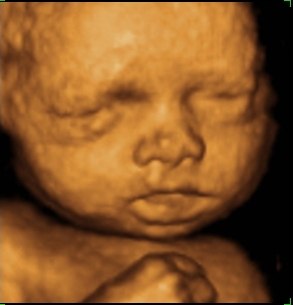

så var vi til 3D scanning i fredags. Så vild en oplevelse.. Hun er bare helt perfekt.

hun vejede 1423g, og så var hun en uge foran så det var da super dejligt at vide at lille pigen har det super og lever luxus derinde i maven

vi var heldige med at hun var rigtig aktiv plus vi også så hende med åbne øjne